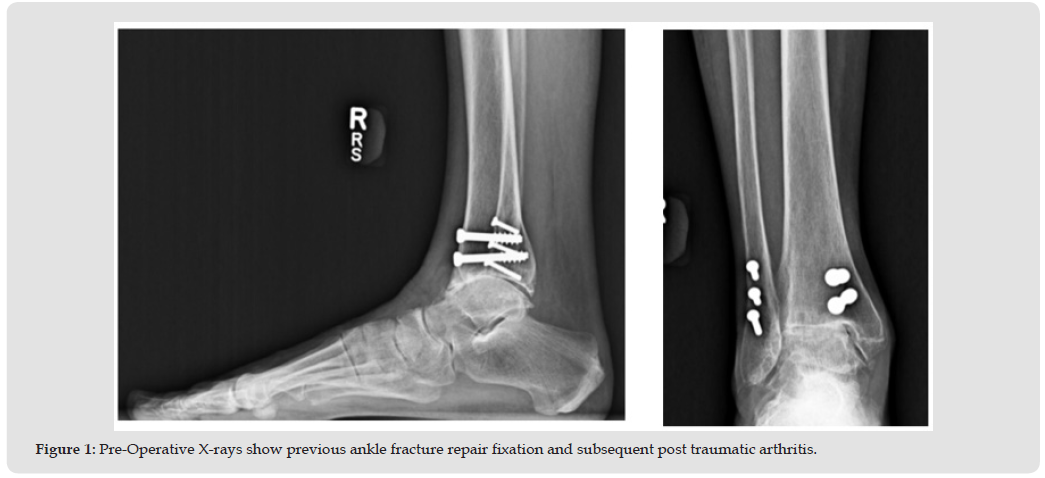

Total Ankle Arthroplasty procedures are becoming more common in properly selected patients. Despite four generations of design improvements, the failure rate over the long term remains stubbornly higher than rates reported in hip and knee arthroplasty. One of the major causes of failure remains aseptic loosening of the implant. Newer generations of synthetic bone grafts with osteogenic properties may have advantages over traditional autograft and allograft and exhibit better handling characteristics. The following case describes the use of a modern generation style TAR in a patient with prior ankle surgery where removal of previous instrumentation led the surgeon to choose Catalyst Bone Graft as a bone void filler to address issues of bone quality and possibly enhance bony ingrowth to the TAR device surfaces. CT scans at the three months follow-up showed Catalyst Bone Graft demonstrated excellent bony ingrowth in and around the implant surfaces setting the stage for further research with this bone graft in larger series of TAR cases with longer follow-up.

The patient is a 66-year-old female (BMI-24) presenting with disabling pain due to post-traumatic ankle arthritis from an ankle fracture and repair surgery which occurred 30 years earlier. The pain has progressed over the years to the point where the patient is no longer able to perform ADLs. Her right ankle alignment is normal. Past surgical incisions both lateral and medial are well healed. There is tenderness of the anterior ankle joint line, with limited ROM 5 degrees dorsiflexion and 10 degrees plantarflexion. She exhibits an antalgic gait (pain causing pronounced limp) despite no ankle instability. Past medical history includes hypertension and hypothyroidism. It was determined that surgery would be necessary for symptom relief and the patient was a suitable candidate for TAR (Figure 1). The surgery consisted of removal of previous hardware from the tibia and prophylactic fixation of the medial malleolus, then implantation of a modern generation style TAR (Paragon 28 Apex3D, Biomet Inc. Warsaw, IN). Catalyst Bone Graft (approximately 2 cc’s) was applied as a bone void filler to the ingrowth/ongrowth surfaces to improve bony incorporation and healing (Figures 2a & 2b). At three months follow-up the patient progresses clinically as expected with physical therapy, and both coronal and sagittal CT scans show excellent bony ingrowth through and around the entire tibia and talus implant surfaces (Figure 3).